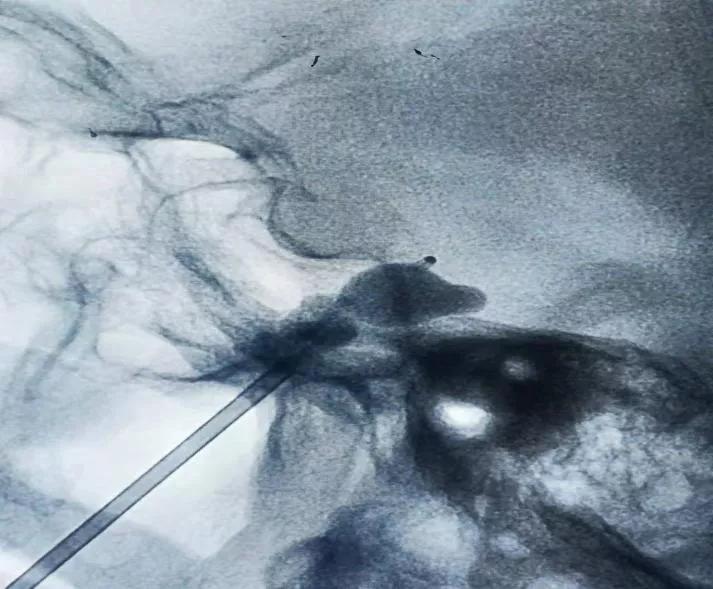

经神经外科功能组王湘副主任医师团队查体和评估,与家属沟通后,决定为杨婆婆行 经皮穿刺三叉神经半月节微球囊压迫术(PBC) 。该手术是在患者嘴角侧切开一个针眼大小的创口,在CT、C臂、X光机等影像设备监视下,用球囊将导致三叉神经痛的神经纤维压迫几分钟,阻断痛觉神经传导,作为一种介入技术,微创三叉神经痛球囊压迫术有效地避免了开颅手术的复杂性与危险性,同时大大缩短了患者的住院时间,减少了治疗费用。手术的长期有效率与开颅微血管减压术无明显差异。尤其适用于 三叉神经痛微血管减压(MVD)术后复发或高龄不能耐受或惧怕开颅手术者 。